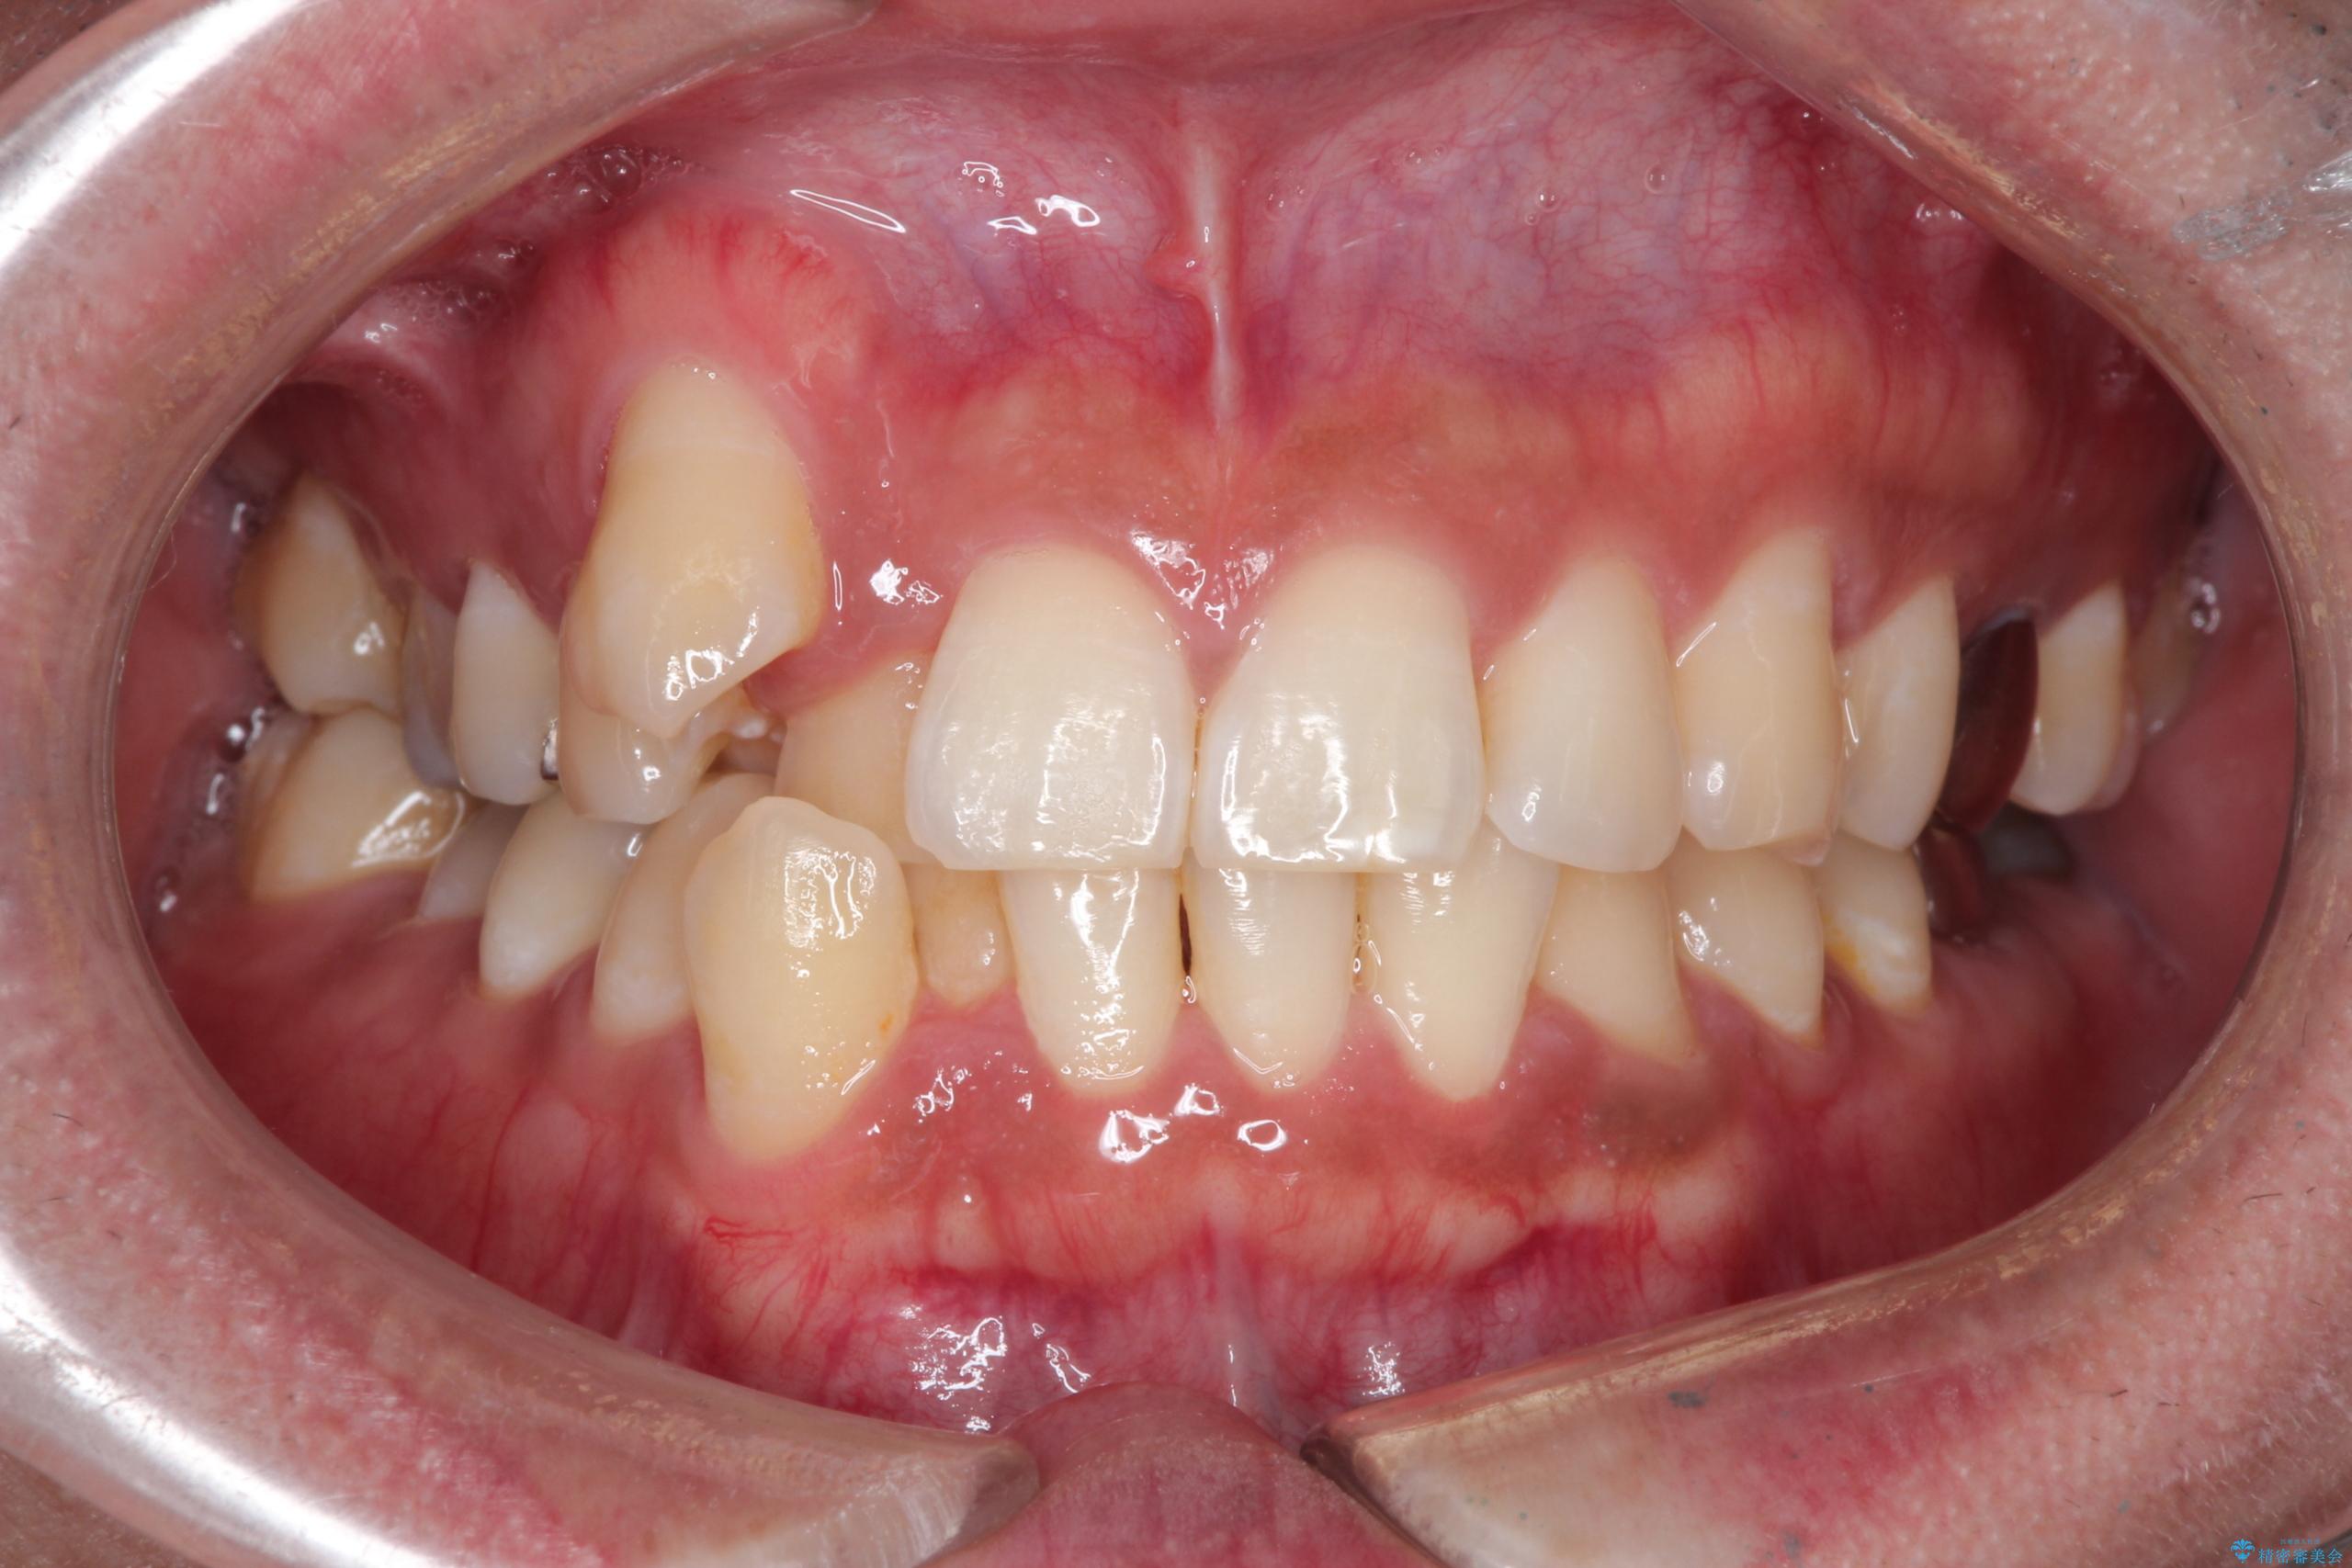

【ワイヤー矯正】八重歯と下の歯の凸凹を治したい

- 主訴:右上の八重歯と、下の歯の凸凹を治したい

上顎右側第一小臼歯と下顎右側第一小臼歯を抜歯しワイヤー矯正を行いました。

右側2級、左側1関係だったため、右側上下第一小臼歯を抜歯し、ワイヤー矯正を行いました。